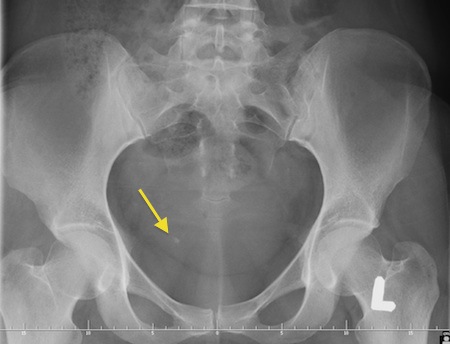

Ustalenie lokalizacji złogu w moczowodzie czasami bywa trudne w warunkach ambulatoryjnych. W przypadku podmiedniczkowego i śródściennego odcinka moczowodu czasami udaje się uwidocznić złóg w czasie USG jamy brzusznej. Złogi uwapnione w większości przypadków widoczne są na zdjęciu przeglądowym jamy brzusznej. Aby dokładnie uwidocznić kamień i ustalić czy cienie mogące być uwapnionymi złogami na zdjęciu zlokalizowane są w moczowdzie należy wykonać urografię lub tomografię komputerową. Czasami konieczne jest ustalenie lokalizacji złogu wykorzystując pielografię zstępującą - u pacjentów z przetoką nerkową - nefrostomią lub pielografię wstępującą.

Fot. Zdjęcia przeglądowe jamy brzusznej pacjentów z kamicą moczowodową. strzałkami zaznaczono złogi w moczowodach.